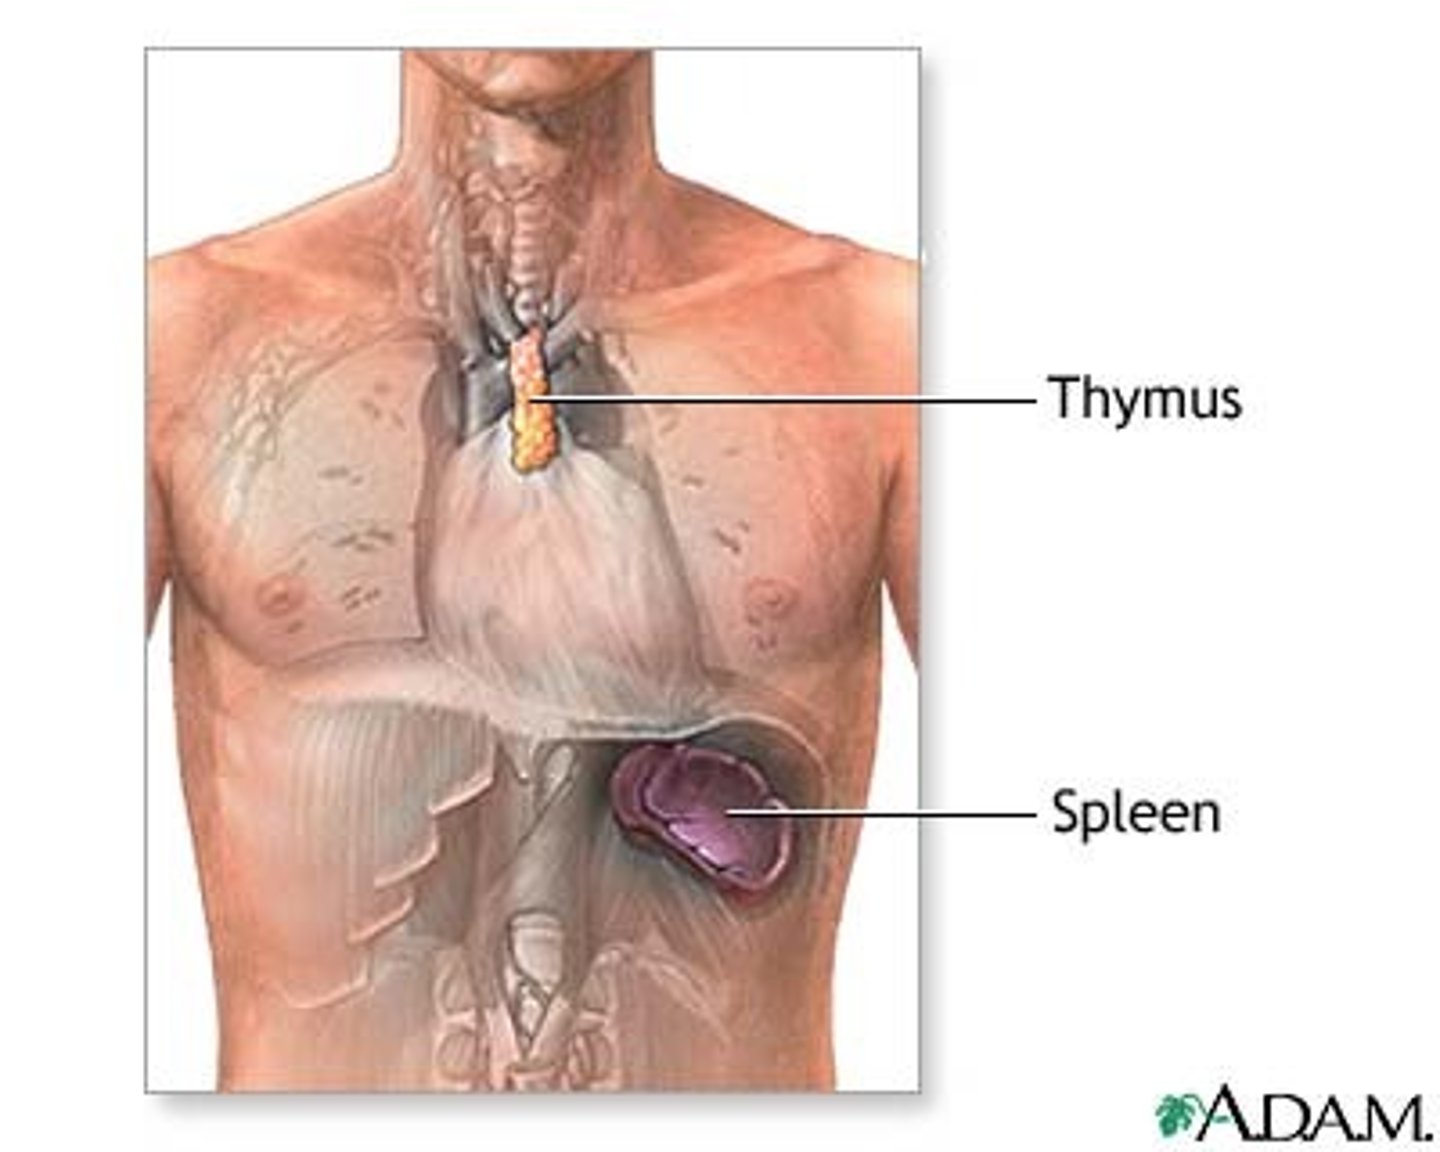

Secondary lymphoid tissues

Lymph nodes, spleen, and mucosa-associated lymphoid tissue (MALT)

What does the spleen do?

Filters blood and removes damaged blood cells --> THE RED BLOOD CELL GRAVEYARD